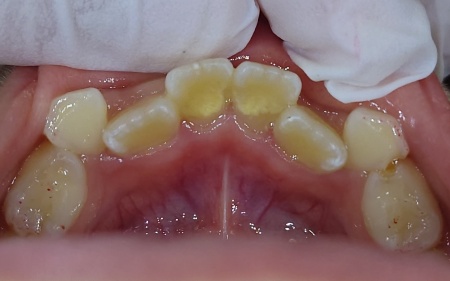

治療後

保険診療内のクリーニングで歯石を除去できることをお伝えし、同意いただきました。

まず超音波を利用した機械や専用器具を用いて、歯に付着しているプラークと歯石を除去するスケーリングを行いました。

その後、プラークや歯石が再び付着しないよう回転するブラシを用いて歯の表面のざらつきを取り除き、なめらかに磨き上げるポリッシングを施して、治療を終了しました。